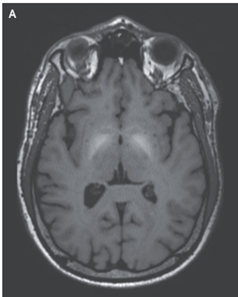

頭部MRI施行。両側大脳基底核に非増強のT1強調高信号を認めた飲みだった(A)。

EDTAの静脈内投与による治療が6ヵ月間行われ、患者の症状は軽快し、MRI上の異常所見も解消された。